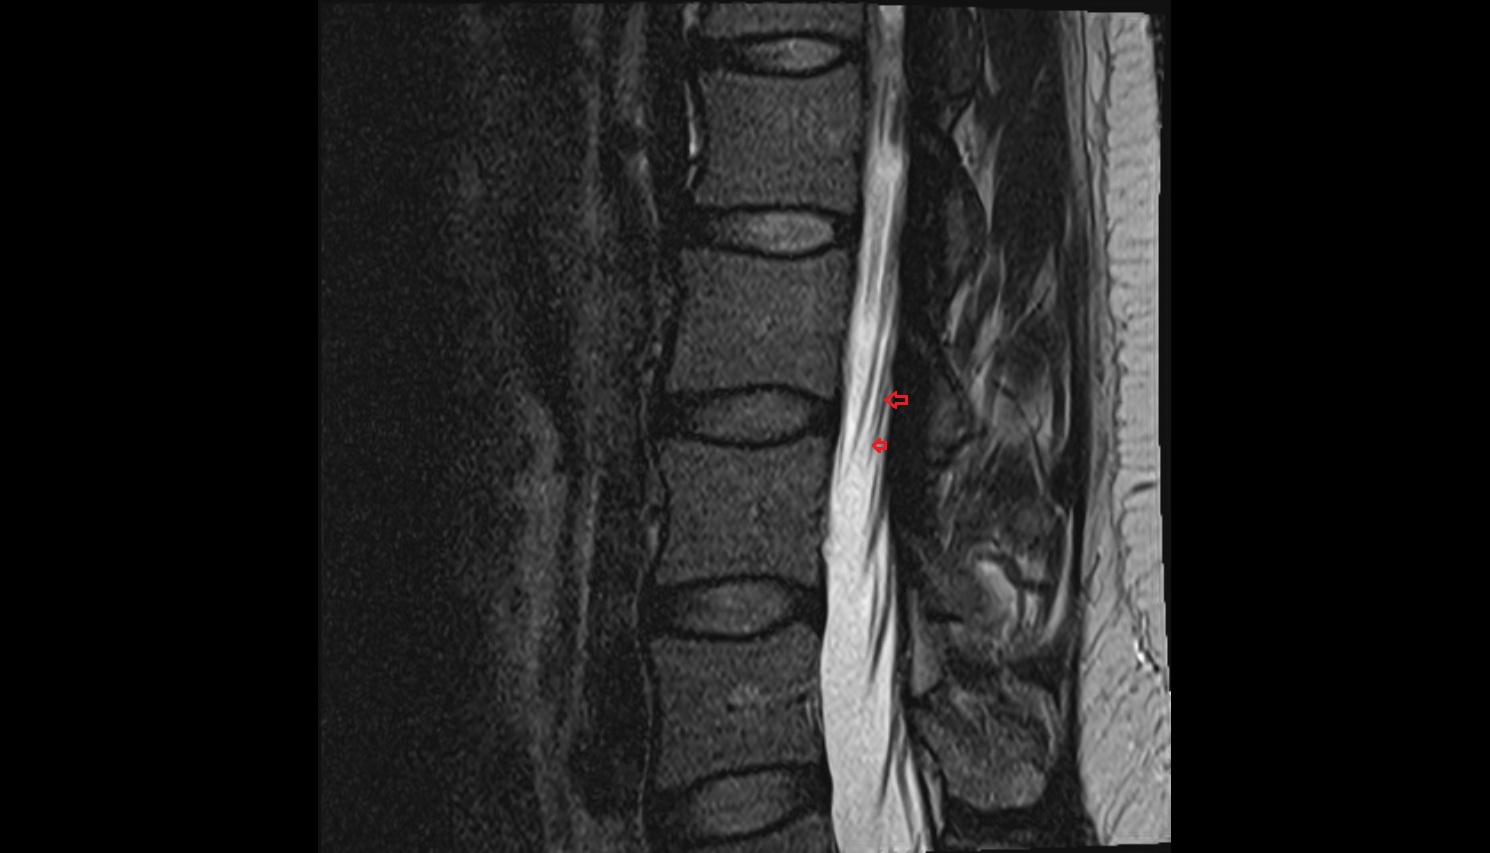

- Cauda equina

- Conus medullaris

- Filum terminale internum